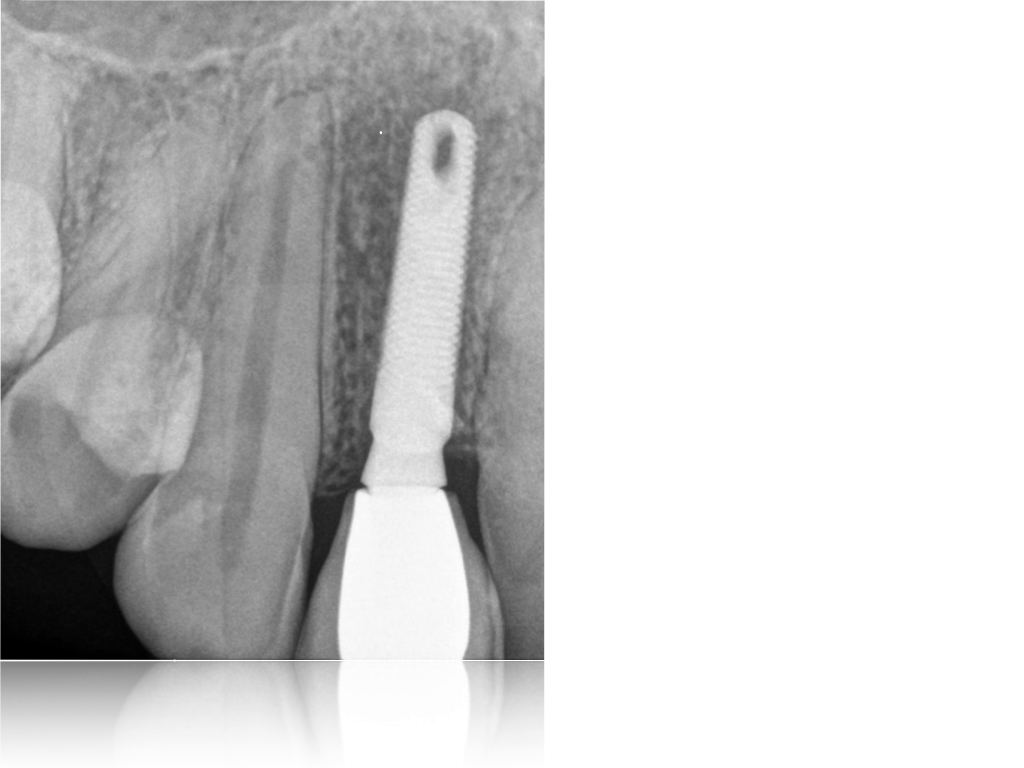

Aurea NP 3.5 mm – Phibo

País de Origen: España Conexión: Hexalobular con cono. Tamaño Plataforma: 3.2 mm plataforma. Tamaño total 3.5 mm. Tipo de cuello: 0.18 mm bisel mecanizado. Altura microespiras 0.3 mm. Peculiaridades de la Espira: Implante autoroscante. Espira mixta. Tamaño [...]